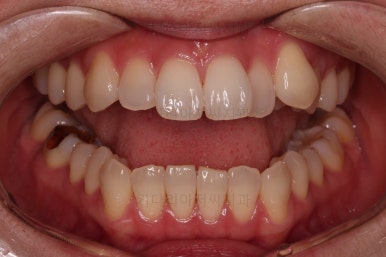

장치를 사용한지 1년 2개월째 사진입니다.

매우 가지런해졌죠.

보통 부산인비절라인은 풀세트로 3회가량 하게 되는데요.

이번 환자분은 1회로도 이 정도의 결과를 만들어 냈습니다.

이 정도의 느낌도 나쁘지는 않지만 미세하게 수정할 부분들이 보여 1회 더 제작하기로 했습니다.

1회 치료를 마친 시점의 얼굴모습인데요.

입매는 그대로이며 치열도 고르고 중앙선도 많이 좋아졌습니다.